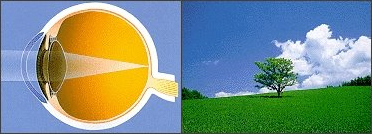

눈 속의 수정체 부분은 사물을 깨끗하고 또렷하게 볼 수 있게 하는데 가장 중요한 기능을 합니다.

이런 수정체가 젊었을 때는 맑다가 나이가 들면서 변화가 생기는 현상 중 하나인

뿌옇게 혼탁기가 증가되어 시력이 떨어지는 질환이 백내장입니다.

정상안 (물체가 선명하게 보인다)

정상안 (물체가 선명하게 보인다) -

백내장안 : 빛이 퍼진다 (물체가 흐릿하게 보인다)

백내장안 : 빛이 퍼진다 (물체가 흐릿하게 보인다)